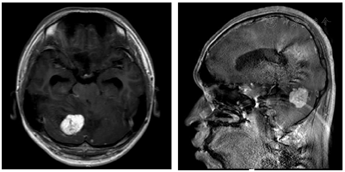

患者,男性,18岁,于2017年7月22日在温州医科大学附属眼视光医院近视激光手术专科就诊,行近视激光手术术前检查,患者无明显不适主诉。眼科检查:矫正视力:右眼:-5.50/-0.25×180=1.0,左眼:-5.25/-1.00×5=1.0。眼压:右眼:15.2 mmHg(1 mmHg=0.133 kPa),左眼:13.9 mmHg。双眼结膜无充血,角膜透明,前房深、房水清,瞳孔圆,直径约2 mm,直间接对光反射存,MG(-),晶体透明,玻璃体絮状混浊。眼底:右眼视盘界清,色淡红,C/D约0.3,A/V=2:3,黄斑中心凹反光未见,后极部视网膜平伏。左眼视盘界清,色淡红,C/D约0.3,A/V=2:3,上方视网膜见一大的视网膜毛细血管瘤及粗大滋养血管,鼻上方及颞上方见多个小的视网膜毛细血管瘤,黄斑中心凹反光未见,后极部周边视网膜平伏。广角激光眼底照相示:左眼见多个视网膜毛细血管瘤及粗大滋养血管(图1)。眼底荧光素血管造影(FFA)示:左眼周边视网膜血管可见多处团样强荧光(图2)。临床诊断:左眼Von-Hippel病。建议患者至综合医院筛查全身肿瘤,并每年于我院随访。患者未按时随访。2021年1月18日,患者因"右眼视物变形3天"复诊。眼科检查:矫正视力:右眼:-4.75=0.6,左眼:-5.00=0.9。眼压:右眼:15.3 mmHg,左眼:15.4 mmHg。双眼眼前节未见明显异常。眼底:右眼视盘水肿,A/V=2:3,黄斑中心凹反光未见,后极部视网膜平伏。左眼视盘水肿,A/V=2:3,上方视网膜见一大的视网膜毛细血管瘤及粗大滋养血管,鼻上方及颞上方见多个小的视网膜毛细血管瘤,黄斑中心凹反光未见,后极部周边视网膜平伏。眼底彩照示:双眼视盘水肿,左眼见粗大滋养血管(图3)。OCT示:双眼视盘水肿。右眼黄斑区视网膜外核层见异常高反射团块,椭圆体带连续性中断(图4)。临床诊断:Von-Hippel-Lindau综合征,左眼视网膜毛细血管瘤,双眼视盘水肿(原因待查)。建议患者至神经外科会诊,排除脑血管母细胞瘤,排除颅内高压。头颅MRI示:小脑右侧半球见约31 mm×23 mm结节样物,小脑扁桃体下缘低于枕骨大孔约11 mm,小脑扁桃体疝(图5)。基因检测示:发现与疾病表型相关的高度可疑变异(图6)。临床诊断:Von-Hippel-Lindau综合征,左眼视网膜毛细血管瘤,双眼视乳头水肿,右侧小脑血管瘤,小脑扁桃体疝。2021年2月4日在上海复旦大学附属华山医院行"脑肿瘤栓塞术+双侧多发小脑病损切除术+右侧侧脑室枕角Ommaya管置入术",病理诊断为:(右小脑)血管母细胞瘤,(左小脑)蛛网膜下腔少量小血管轻度增生。术后1月余(2021年3月22日)复查,右眼视物变形较前好转,双眼矫正视力提高(右眼0.6,左眼1.0),双眼视乳头轻度水肿(图7)。OCT示:右眼黄斑区视网膜外核层异常高反射团块消失,正常形态恢复(图8)。术后5月余(2021年7月12日)复查,双眼视乳头水肿较前好转(图9)。术后7月余(2021年9月15日)复查,右眼矫正视力0.8,左眼矫正视力1.0,双眼视乳头水肿基本恢复(图10)。建议患者行左眼视网膜激光光凝术治疗视网膜毛细血管瘤,患者因其可能风险拒绝。